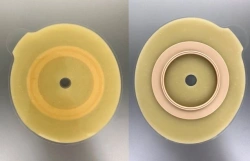

Medical product is intended for use in colostomies, ileostomies and urostomies for hermetic and secure attachment of stoma bags to the skin of the anterior abdominal wall, as well as to protect the skin of the peristomal area from stoma secretions and preserve the physiological functions of the skin due to the absorption of natural skin moisture (sweat, sebum).